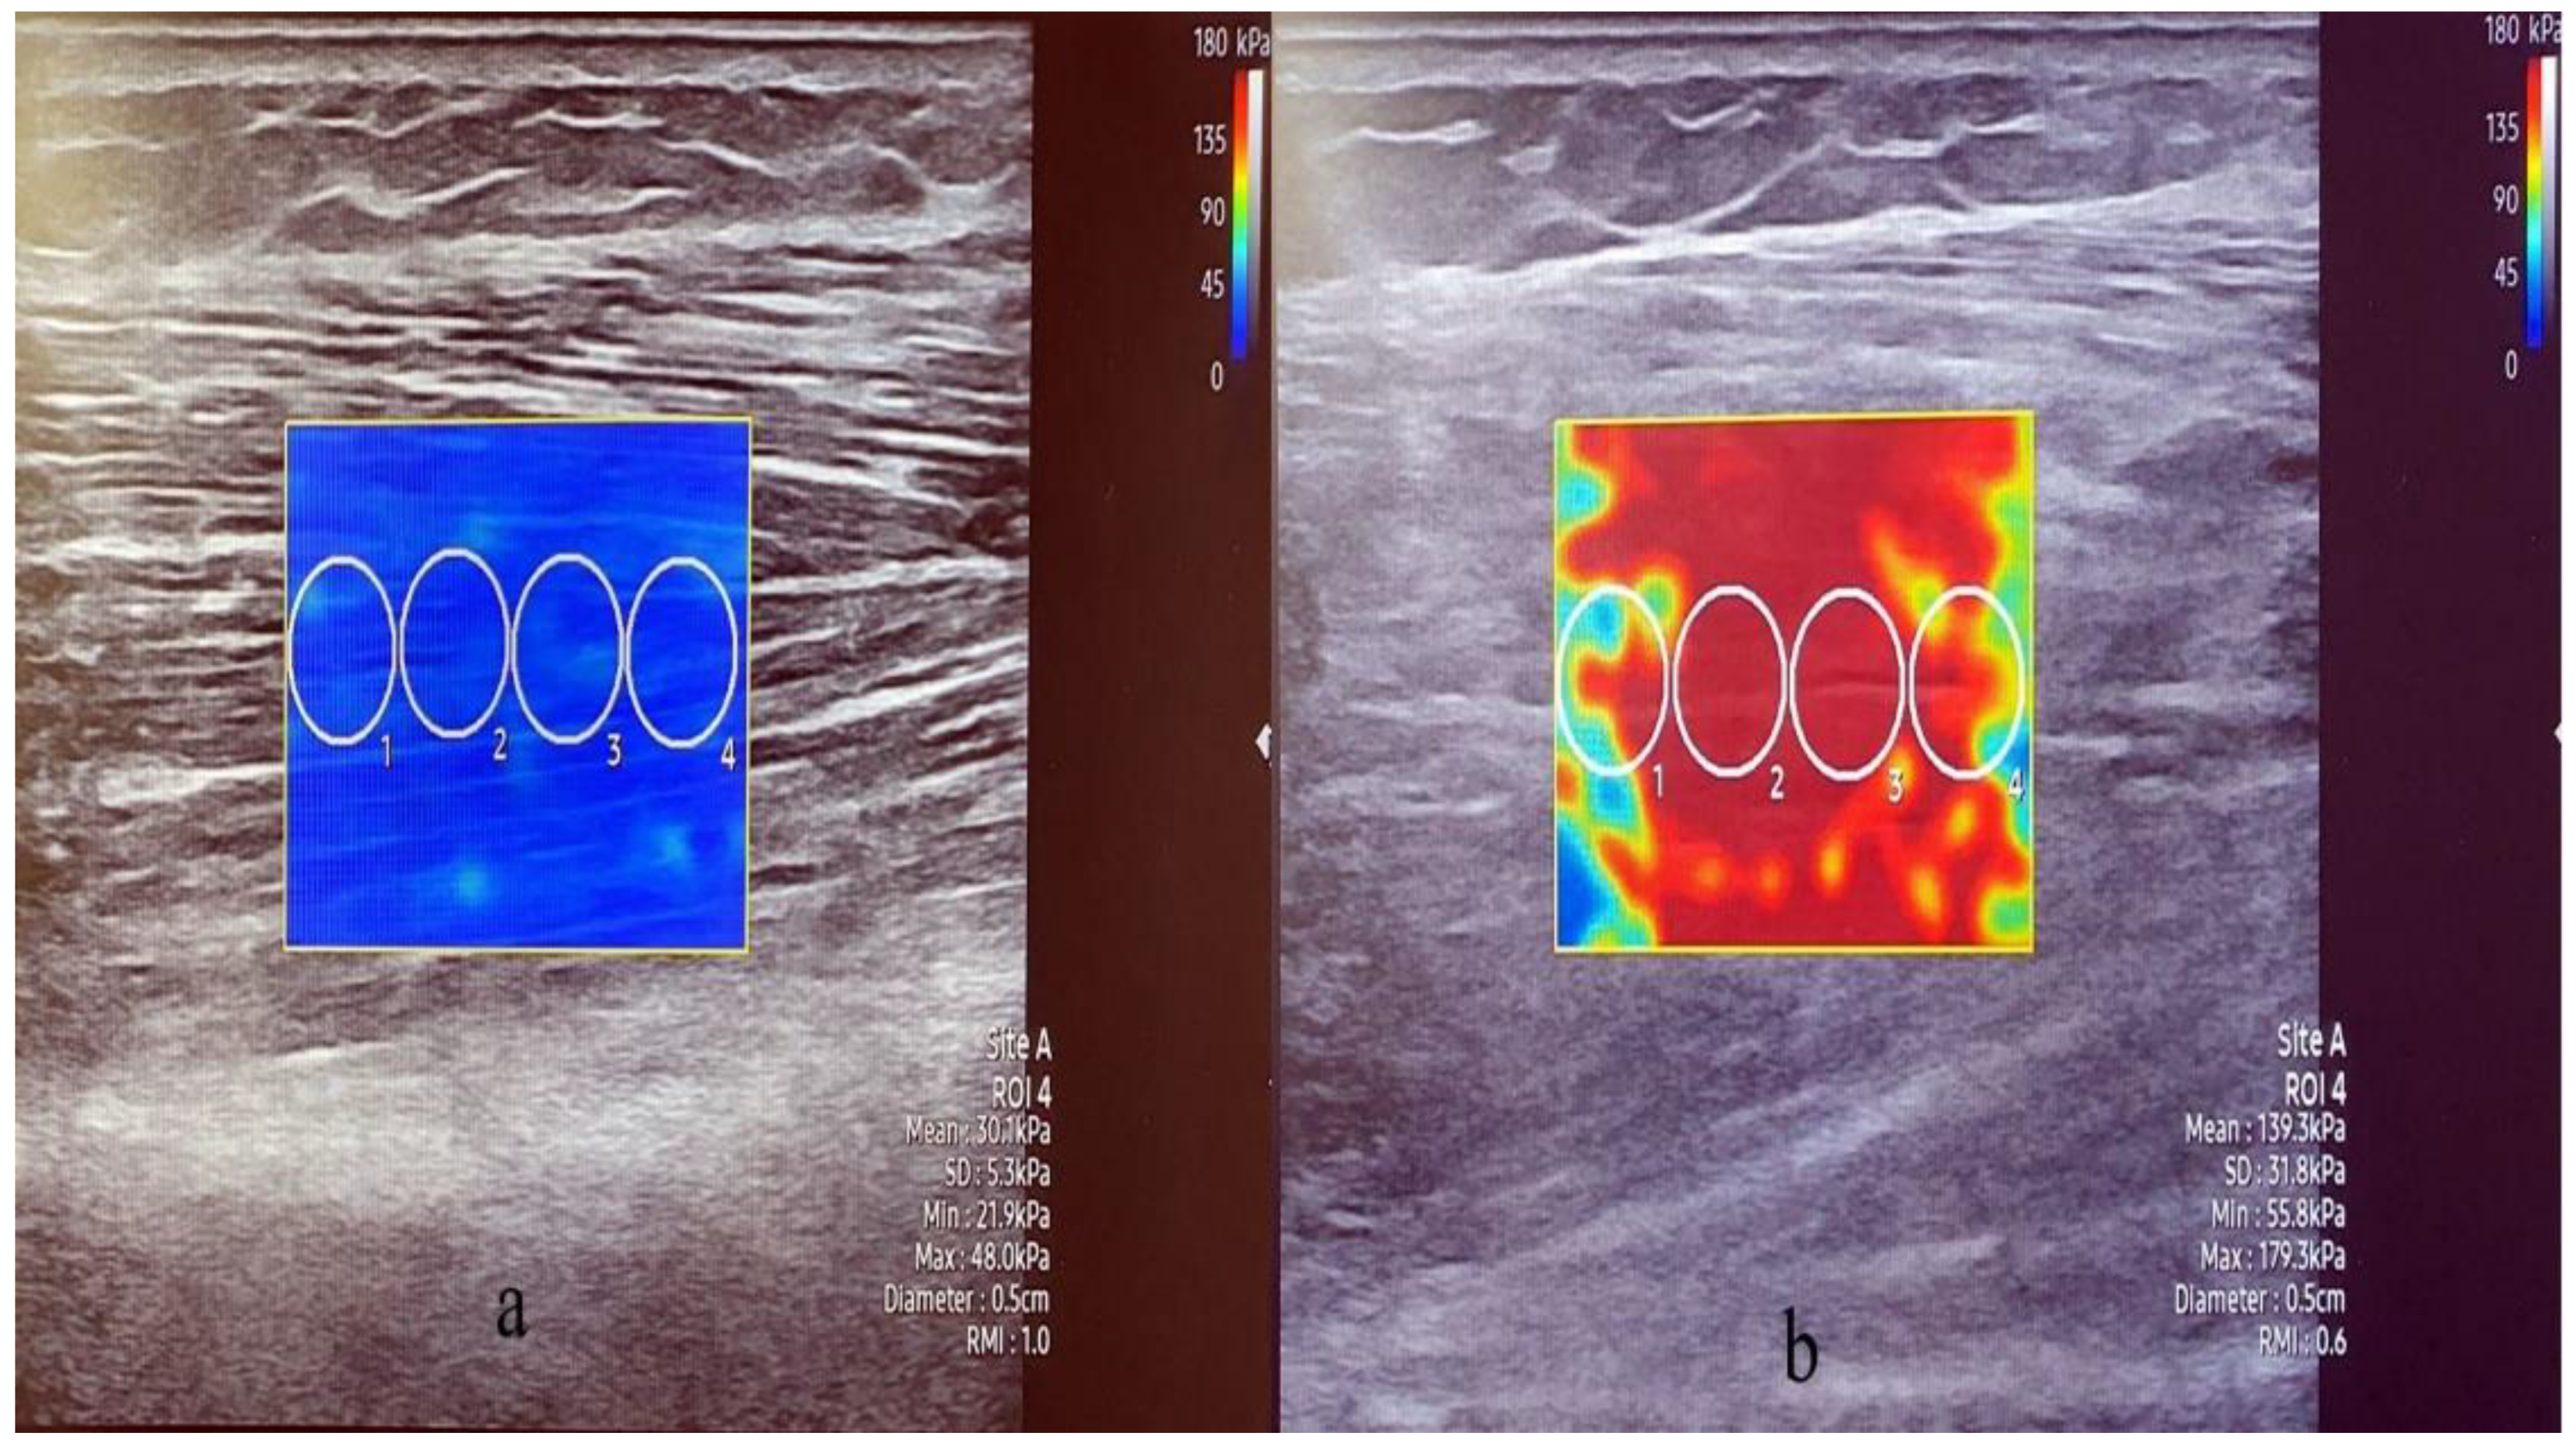

2.3.4. Stiffness and Thickness of the Muscle